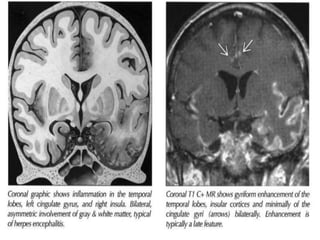

Herpes simplex encephalitis

– Most common viral encephalitis

– HSV 1usually activation of latent infection in

trigeminal ganglion

(in neonates- HSV 2)

– Fulminant, necrotising, hemorrhagic; considerable mass

effect.

– Mortality up to 55%.

– Predilection for limbic system - inferomedial temporal

lobe, orbital surface of frontal lobe , insular cortex,

cingulate gyrus

– Sequential bilaterality – highly suggestive

• Imaging

– CT – often normal in early disease. In adults, CT classically reveals

hypodensity in the temporal lobes either unilaterally or

bilaterally, with or without frontal lobe involvement, usually with

mass effect. Changes may be minimal in the first 2-3 days despite

severe neurological impairment and should be carefully sought.

Hemorrhage appear slightly later.

– CECT – ill defined patchy or gyriform enhancement

– In chronic stage – large low density areas with associated local

atrophy in the affected region.

• MR – more sensitive to white matter changes;

shows the lesion to be more extensive than

they appear on the CT; can identify at earlier

stage as gyral edema, temporal lobe

hyperintensity in T2WI, +/- enhancement

• hemorrhage – increased signal intensity on

T1WI and usually implies extensive necrosis.

• MRI also shows extensive periventricular

signal changes not apparent on CT.